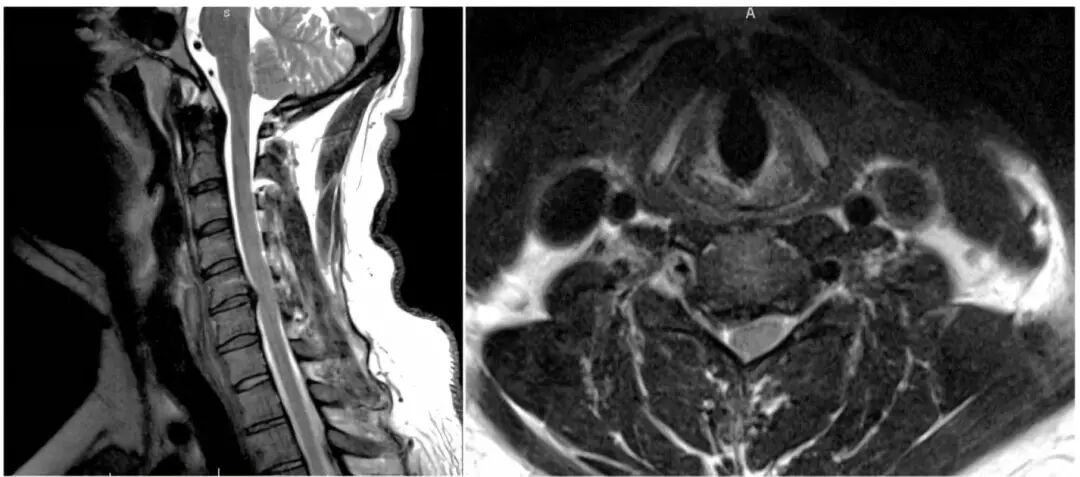

通过以下这个病例阐述了与单节段颈椎间盘骨赘复合体引起的神经根型颈椎病的评估和手术治疗相关的问题。

男性,27岁,6月前出现右臂向拇指和示指的放射性疼痛。

保守治疗失败:包括物理治疗和非甾体类抗炎药(NSAIDs)。

感觉:沿着右侧C6分布区的轻触觉减弱